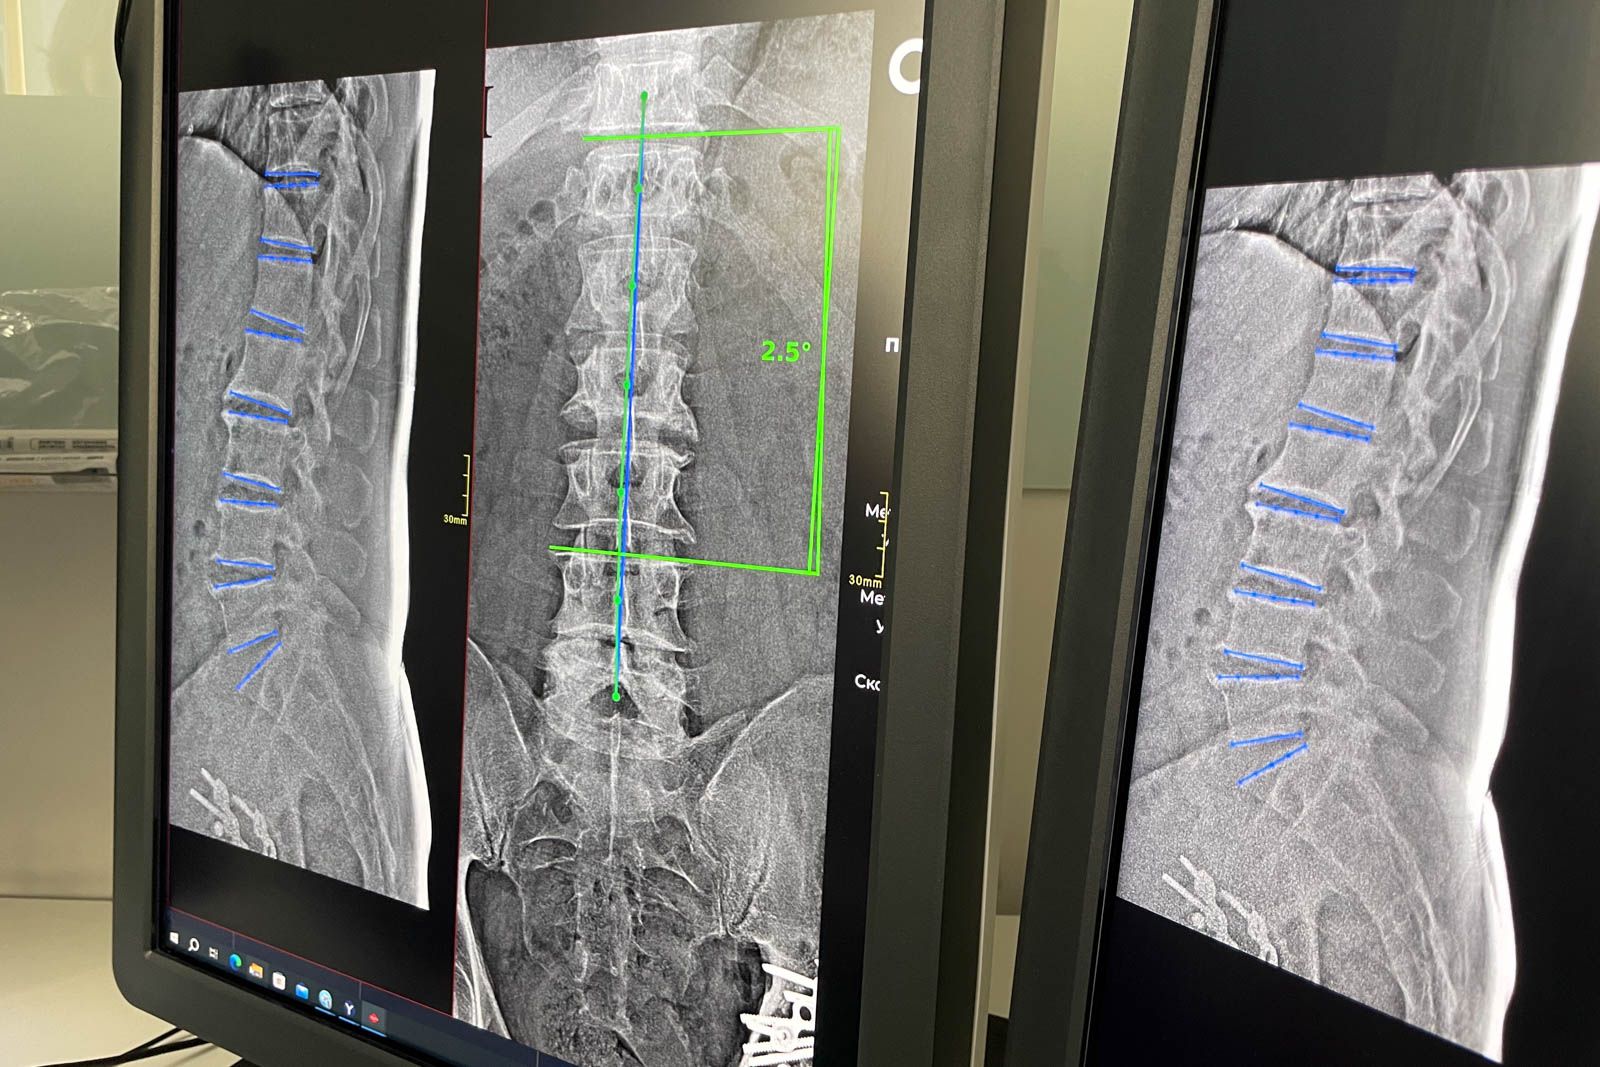

Нейросети автоматически анализируют рентгенограммы позвоночника, выявляют признаки смещения и мгновенно выполняют необходимые измерения, что позволяет врачам быстрее и точнее ставить диагноз. Это значительно сокращает время на подготовку заключения и способствует более оперативному назначению лечения. На сегодняшний день с помощью ИИ было обработано более 12 миллионов исследований. Нейросети также помогают находить признаки различных патологий на маммограммах, КТ, МРТ и рентгеновских снимках, включая рак легких, пневмонию, остеопороз, аневризму аорты, ишемическую болезнь сердца, инсульт и легочную гипертензию. Точность диагностики, обеспечиваемая искусственным интеллектом, сопоставима с результатами врачебного обследования.